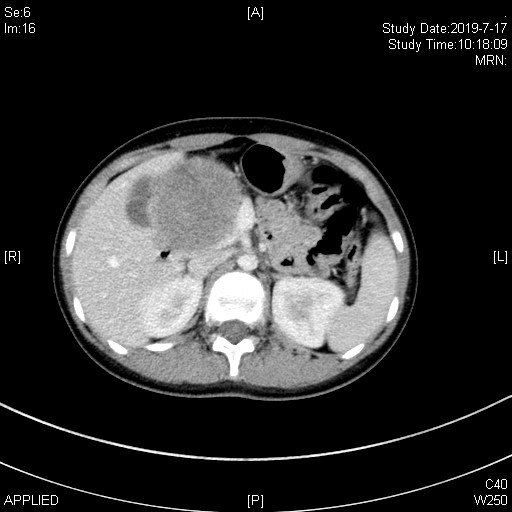

患者张**,女,11岁8个月,因“上腹部胀痛不适3个月”就诊当地医院,腹部ct提示胰头巨大肿瘤、压迫周围血管并导致肠系膜上静脉狭窄变型。为手术治疗转诊我院!

术前ct:

患者术前诊断考虑“胰头巨大实性假乳头状瘤”,治疗需行胰十二指肠切除术!但该手术风险大,术后并发症发生率高,且患者肿瘤巨大、压迫血管致手术难度增加;患者年龄较小,围手术期治疗棘手!为此,我们做了充份的预案!于2019年7月24日成功进行了保留幽门的胰十二指肠切除术(保留幽门可最大程度保留营养吸收,为患者以后生长发育提供条件)。